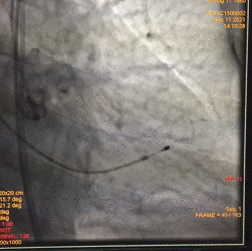

术中影像

图片

根部造影

球囊预扩

瓣膜释放至2/3造影观察

瓣膜释放后形态欠佳

经球囊后扩后瓣膜形态良好

手术结果

术后造影及超声探查未见瓣周漏,跨瓣压差术前183mmHg,术后几乎无压差,术中及术后未出现相关并发症,手术圆满完成。